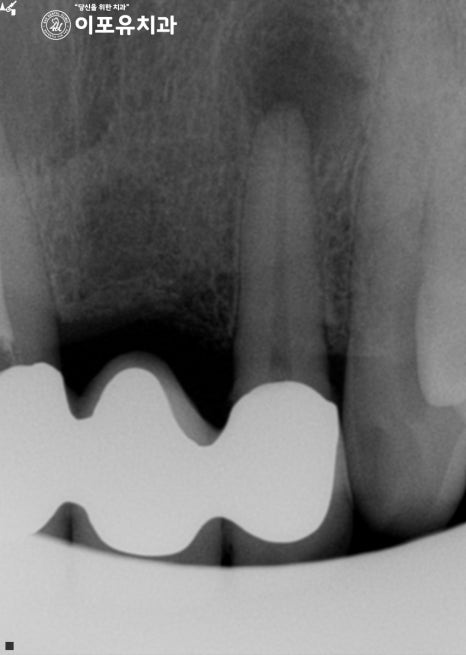

단순히 신경치료를 한다 해서 해결될 문제가 아니라,

잇몸을 절개하여 농양을 없애야 되는 상황이었죠.

이렇게 잇몸에 있는 농양을 절개하여 없애는 과정은

‘구강외과’전문의에게 가는 것이

예후에 있어 좋은 방법이란 판단이 들었습니다.

신경치료를 하는 것은 당연히 자신 있지만,

이분의 경우 단순히 그 문제만이 아니었습니다.

그래서 농양을 없애는 수술을 먼저 진행할지,

근관치료를 먼저 해야 될지 결정을 해야 되는데요.

이때 근관 세척 및 충전으로도 줄어들 크기가 아니라..

구강외과 전문의에게 가는 것이

올바른 판단이란 생각이 들었죠.